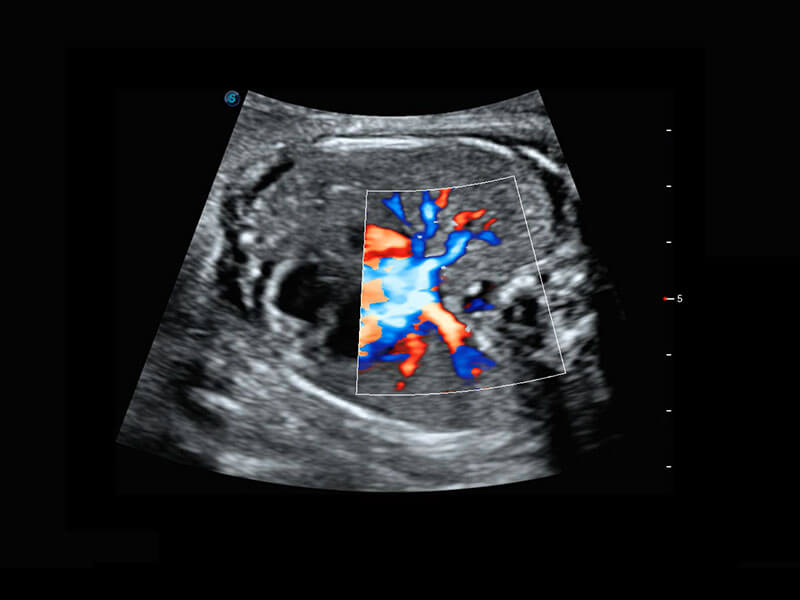

P60搭载宽频带线阵探头、宽景成像、弹性成像技术,为您提供乳腺应用方案。P60支持高频相控阵探头、线阵探头、腹部高频探头、腹部微凸探头等,丰富的探头群搭载敏感的彩色血流成像,适用于新生儿多种脏器检测要求,满足新生儿筛查需求。

新生儿肝血管癌

新生儿心脏